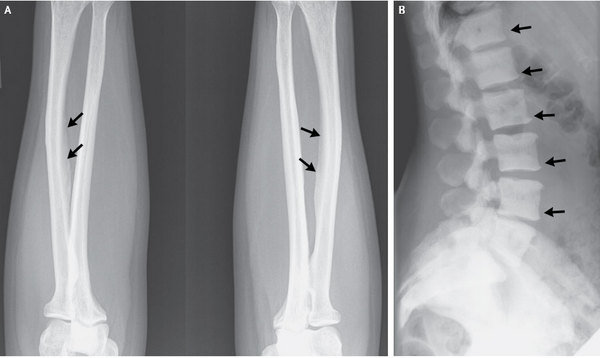

X-rays revealed areas of very dense bone on the spinal vertebrae and calcifications of ligaments in her arm, said study researcher Dr. Sudhaker D. Rao, a physician at Henry Ford Hospital who specializes in endocrinology and bone and mineral metabolism.

The researchers suspected the woman had skeletal fluorosis, a bone disease caused by consuming too much fluoride (a mineral found in tea as well as drinking water).